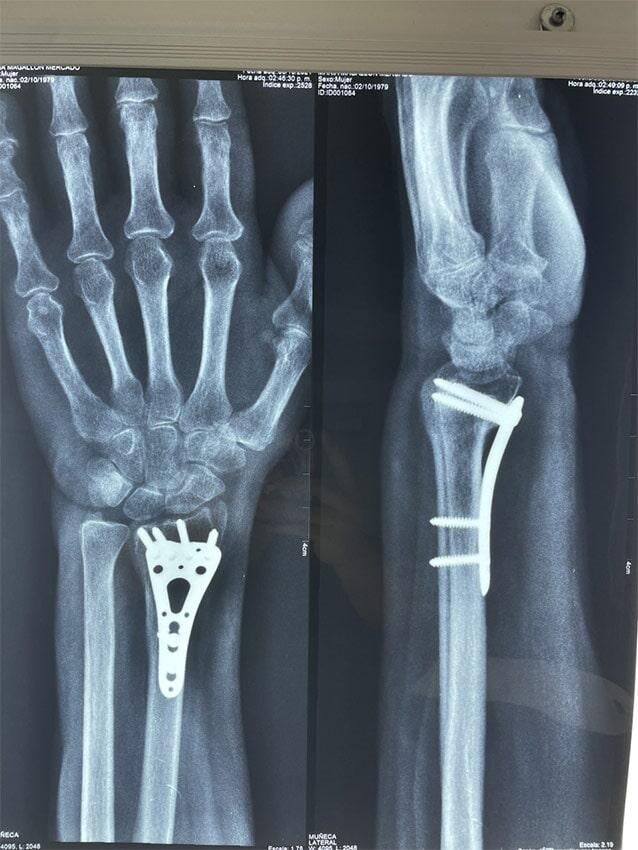

ButtonARTROUPN - Fracturas

ButtonARTROUPN -Fracturas complejas

ButtonARTROUPN - Fracturas y luxaciones